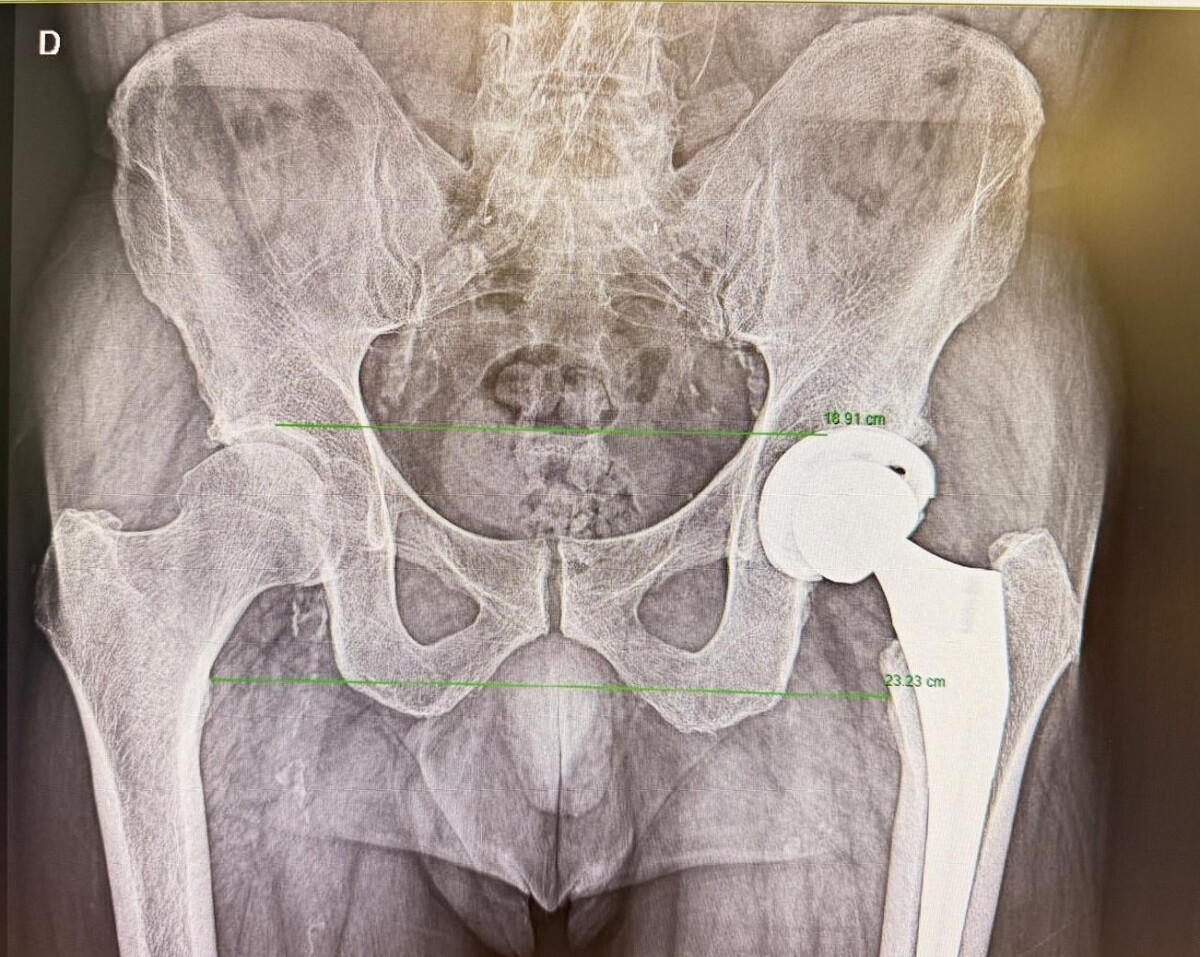

Madrid, 24 de febrero de 2026.- El reemplazo de cadera es una de las cirugías ortopédicas más habituales para tratar patologías como la artrosis avanzada, fracturas o deformidades que generan dolor persistente y limitación funcional. Su objetivo es aliviar el dolor y recuperar la movilidad, mejorando de forma notable la calidad de vida del paciente.

En los últimos años, la cirugía de prótesis de cadera ha experimentado una clara evolución, no tanto por el implante en sí, sino por los avances en las técnicas quirúrgicas, el control del dolor y los protocolos de recuperación. En este contexto, comienza a abrirse paso un nuevo escenario: la cirugía de prótesis de cadera ambulatoria, en la que el paciente puede regresar a su domicilio el mismo día de la intervención.

La llamada vía anterior en la prótesis de cadera no es una técnica nueva, aunque en los últimos años ha ganado popularidad. A diferencia de otros abordajes, permite acceder a la articulación entre planos musculares, sin necesidad de cortar músculos, lo que se traduce en un postoperatorio inmediato más rápido.

“La gran ventaja de la vía anterior es que el paciente tiene menos dolor en los primeros momentos tras la cirugía y puede iniciar antes la movilización”, explica el Dr. Martín Buenadicha. A medio plazo, los resultados funcionales tienden a equipararse con otras vías, pero esta recuperación inicial más ágil resulta especialmente relevante cuando se plantea un alta precoz.